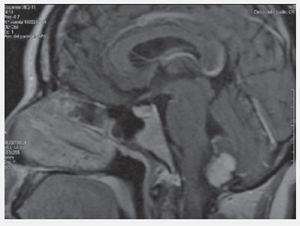

Abdomen globoso, a expensas de panículo adiposo, no adenomegalia, no se palpan masas, dolor a la palpación en epigastrio. Glucosa: 76 mg/dL, Creatinina: 0.87 mg/dL, amilasa y lipasa normales, TC abdomen: Lesiones quísticas de páncreas y ambos riñones. IRM Abdomen: Lesiones quísticas en páncreas y ambos riñones. IRM de cerebro: Hemangioblastoma en cerebelo.

Figura 4. IRM Hemangioblastoma cerebral.